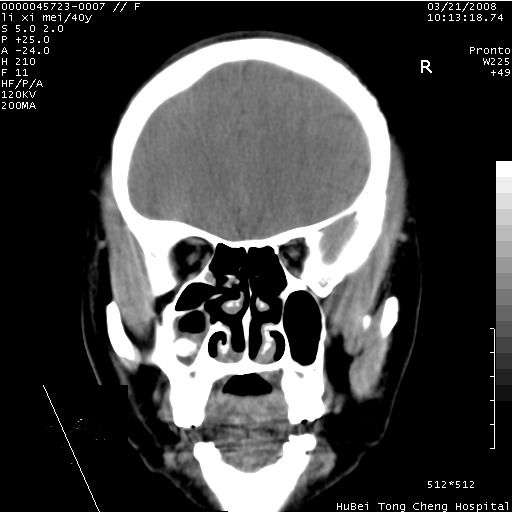

以下是引用卜一在2008-3-21 20:18:00的发言:[br]双侧上颌窦炎症,双下鼻甲肥大!不除外霉菌感染!

以下是引用qiuleiyu在2008-3-21 21:46:00的发言:[br]支持;上颌窦炎,窦内高密度影,建议横断位观察与上颌窦前壁关系。除外骨源性病变。